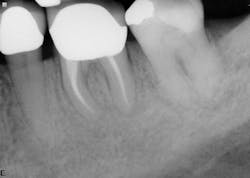

Healing is noted on the six-month follow-up (figure 4).